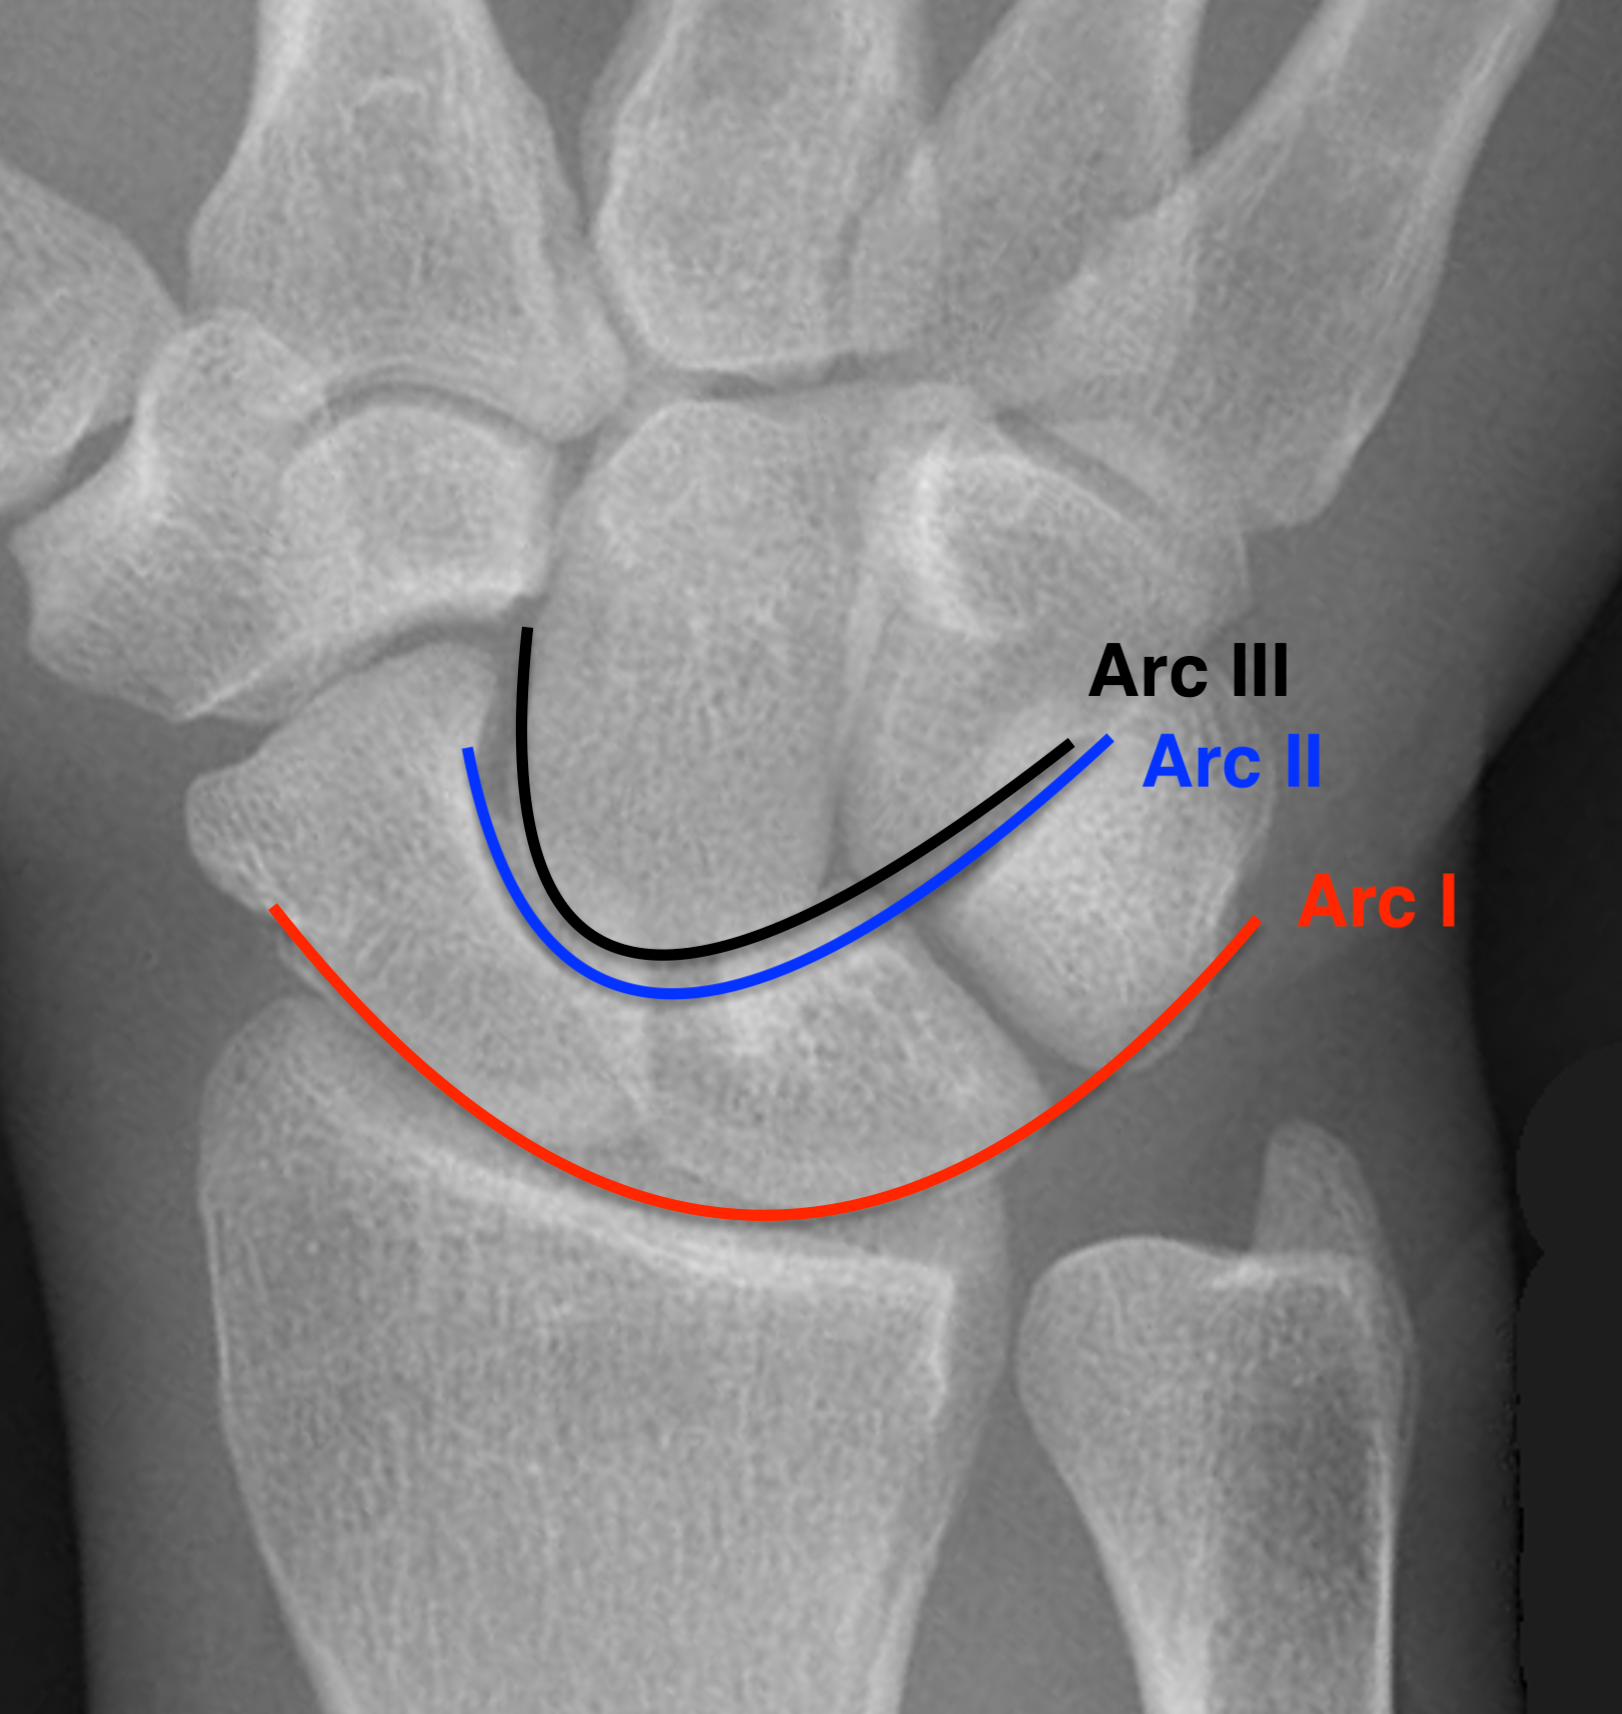

Gilula carpal arcs

Normally there are 3 smooth carpal arcs on PA xray

Arc I: Proximal cortical margins of proximal carpal row Arc II: Distal carpal margin of the proximal carpal row Arc III: Proximal cortices of the capitate and hamate |